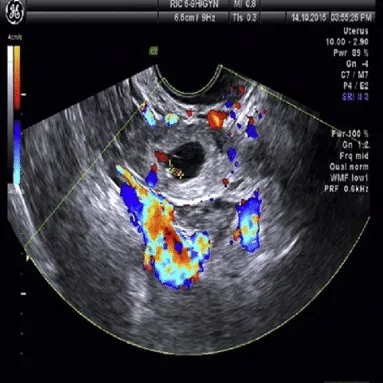

2. Ultrasound Transvaginal (TVS)

Ultrasound Transvaginal (TVS)

Teknik : Merupakan prosedur ultrasound di mana ia dilakukan dengan cara memasukkan probe sepanjang 5cm ke dalam vagina.

Jenis ultrasound : 2D hitam putih

Tujuan pemeriksaan :

- Memeriksa rahim dan kilang telur (ovari) dengan gambaran yang jelas.

- Mengesan cyst.

- Mengesan ketumbuhan di rahim seperti fibroid, endometrioma atau polyp.

- Mengesan awal kehamilan.

- Mengesan kandungan luar rahim (ectopic pregnancy).

Persediaan : Pastikan pundi kencing kosong sebelum pemeriksaan.